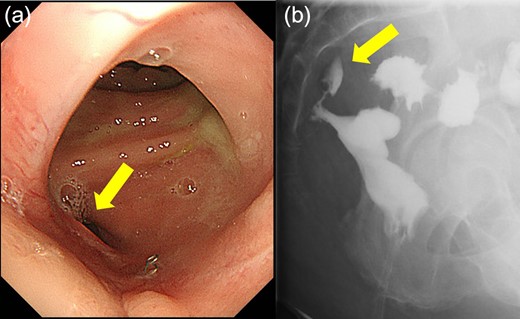

Case 1 was a 71-year-old man with a BMI of 29.7 kg/m2. Laparoscopic low anterior resection (LAR) and ileostomy was performed for rectal cancer in 2017 years. Postoperative fever and lower abdominal pain were noted, and colonoscopy was performed, and anastomotic leakage was noted with a correction of about 1/2 around the 6 o’clock direction of the anastomotic region, and fistula and formation of a large abscess cavity. After identification (Fig. 1), a tube was inserted for drainage and conservative treatment was performed. The patient was discharged on POD 46. Four months after the operation, marked improvement in the abscess cavity was noted but still remained (Fig. 2a and b). Anastomotic leakage was almost improved by colonoscopy at 17 months after surgery, but at the preference of the patient we performed colostomy 22 months after surgery (Fig. 3). It took a long time to improve intestinal movement of the colon because the large intestinal tract had not been used for a long time, and conservative treatment was performed using a nasogastric tube for paralytic ileus. Diet was initiated 7 days after surgery, and the patient was discharged from the hospital 14 days after surgery. The Wexner score [2] was 19 points one month after closure, 17 points 3 months after the operation and 16 points after 6 months after the operation, and severe anal dysfunction was observed, but gradually improved.

Colonoscopy revealed a true lumen (circle), an anastomotic site (triangle) and a cavity due to suture failure (arrow).